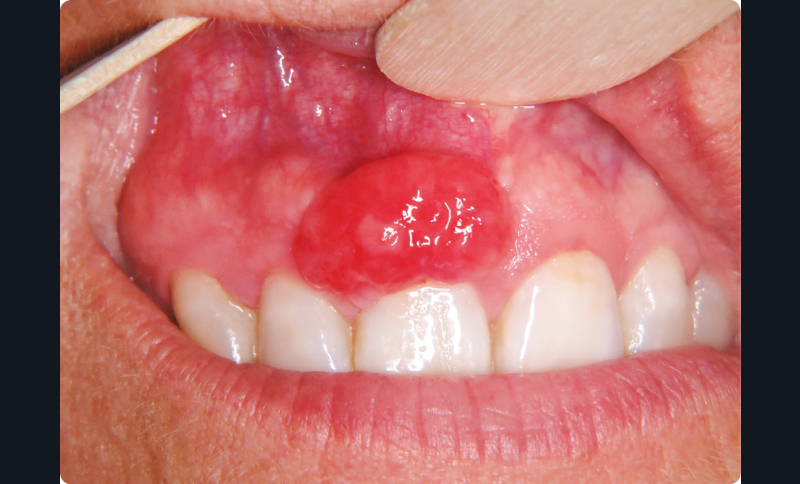

• À l’inspection, on observait un nodule érythémateux d’environ 1 cm de diamètre, de surface lisse, d’aspect pédiculé, développé aux dépens de la papille gingivale située entre 11 et 12. La palpation du nodule de consistance ferme provoquait un saignement.